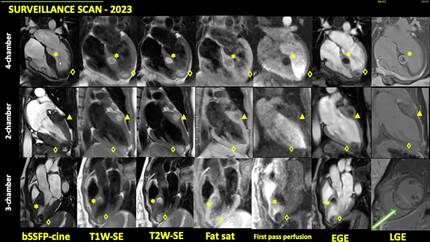

Recurrence of liposarcoma metastasis to cardiac interventriculat septum